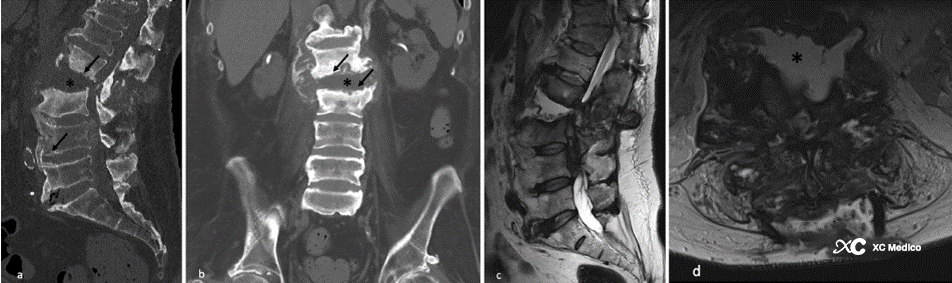

Нейрогенный спондилит (NS), деструктивная прогрессивная артропатия, возникает после потери ощущения и проприоцепции. Наиболее распространенной причиной является травматическое повреждение спинного мозга, которое составляет 70% случаев. Другие причины включают сахарный диабет, кавернозное заболевание спинного мозга и другие неврологические расстройства, такие как перинеальная мышечная дистрофия и синдром Гийлена-Барре. Из-за роли грудных и поясничных соединений в несущих веса они являются наиболее часто вовлеченными участками.

Типичными проявлениями NS являются фрагменты кости, межпозвоночные неровности суставов и несоответствия, приводящие к проскальзыванию тела позвонков, множественным конечным пластинкам и небольшим эрозиям сустава, а также к сохранению плотности кости при склерозе, а также массах мягких тканей.

Примечание: 58-летний мужчина с невропатическим позвоночником. (а) Сагиттальные и (б) корональные компьютерные томографические реконструкции показывают множественные конечные пластины поясничного позвонка и эрозии суставных синовиальных суставов (стрелки) с фрагментами кости. Разрушение блока межпозвоночного диска L2-L3 с расширением межпозвонкового пространства (звездочка). (C) Сагиттальные и (D) осевые T2-взвешенные магнитно-резонансные последовательности, подтверждающие расширение межпозвоночного пространства L2-L3. Значительные изменения пораженного спинного мозга сзади к L2-L3-L4. Существует также выпот в мягких тканях сзади и спереди к остистым процессам (звездочки).